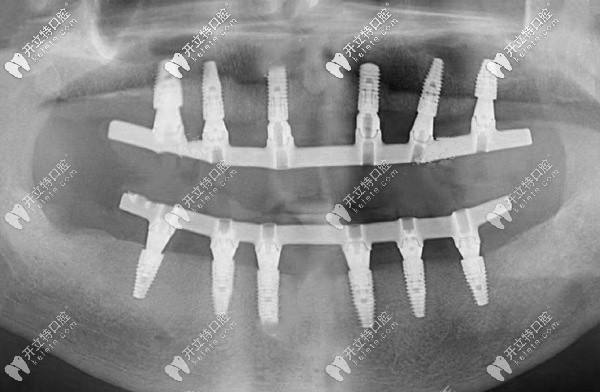

首先,給大家說(shuō)明一下,all-on-6全口種植牙,在上、下頜會(huì)各植入6顆種植體,植體上部會(huì)搭配連橋冠來(lái)恢復(fù)全口牙的生理功能。

通常可以當(dāng)天種牙、當(dāng)天用,因此,被稱為即種即用。

all-on-six即刻種植牙的全景片

(這就是all-on-six即刻種植后的全景片)